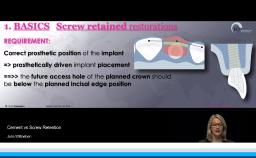

This lecture describes a well documented case series on the effect of different abutment designs for single tooth implant restorations. The long term crestal bone level changes were analyzed retrospectively to understand the good or bad effects of abutment designs and materials. R. Oretti, with his clinical experience, provides clinical recommendations regarding the abutment designs while treating single missing teeth either with a tissue level or a bone level implant. Insights on the abutment material selection, implant-abutment junctional wear, and the ideal abutment contours are explained to achieve the long-term success of the implant restorations.

- explain abutment design and material considerations for long-term clinical success

- recognize the implant-abutment junctional architecture and emergence profile for clinically favorable soft tissue contours